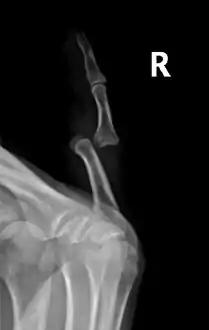

Dislocation of the left index finger

Radiograph of right fifth phalanx bone dislocation